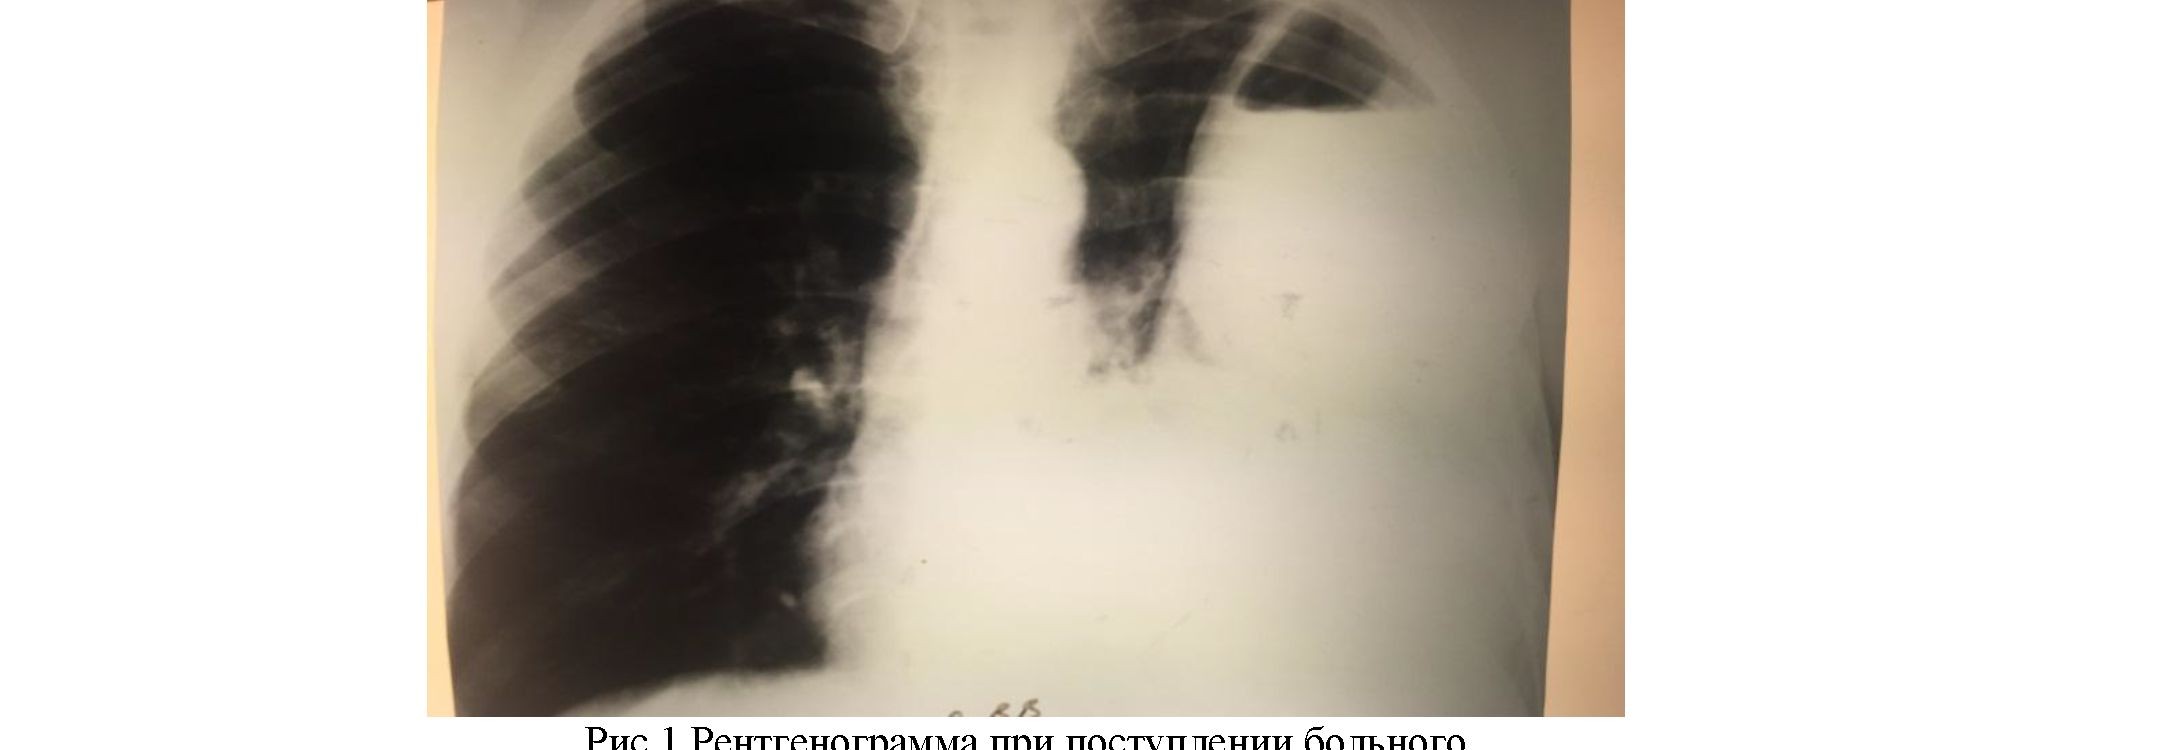

Фотографии, демонстрирующие обнаруженное усиление легочного рисунка

Раздел: Фотодневник открытий